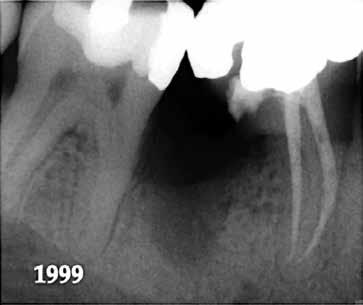

10. ábra: A periapikális felvételen egyértelműen megmutatkozik a 46-os és 47-es fogak között kialakult csontos defektus, valamint a gyökereket fedő parodontális rostok károsodása. – 11. ábra: A disztális gyökér amputációját követően a csonthiány kiterjedése látszólag tovább növekedett. – 12. ábra: A 22 évvel később készített kontrollfelvételen jól megfigyelhető a csontos defektus telődése, valamint új kortikális csontállomány kialakulása.

Gyökéramputációt főként a furkáció érintett nagyőrlő fogak ellátása során szoktunk alkalmazni. Derks és mtsai. vizsgálatában a gyökéramputált nagyőrlő fogak közel 80%-a 20 évvel a beavatkozás elvégzését követően is megtartott volt. 1998 októberében egy 39 éves férfi páciens a jobb alsó kvadránsban jelentkező ínyérzékenység miatt kereste fel rendelőnket. A klinikai vizsgálat során jobb alsó első és második nagyőrlő fog között (46–47) nagy kiterjedésű csontveszteséget észleltünk. Ettől eltekintve a teljes fogazat parodontális státusza megfelelőnek bizonyult. A jobb alsó kvadránsban végzett szenzibilitás vizsgálat során arra az eredménye jutottunk, hogy a 46-os fog vélelmezhetően elhalt (10. ábra).

A páciens beleegyezését követően a 46-os fog disztális gyökere, a disztális gyökér felett lévő koronális rész megőrzése mellett rezekcióra került (11. ábra). A rezekciót követően a referáló orvos a 46. és 47. fogak koronáját Ribbond szalag és kompozit segítségével egymáshoz rögzítette. A sebészi beavatkozást követően 22 évvel készült kontrollfelvételen a lézió csontos telődése, kortikális csontállomány kialakulása, valamint a furkáció körüli csontos regeneráció volt megfigyelhető (12. ábra) A károsodott fogak megtartására szolgáló lehetőségek fejlődésének, valamint az implantátumok behelyezésével kapcsolatos rizikófaktorok jobb megértésének köszönhetően ma már más szemmel vizsgáljuk a fogak eltávolításának szükségességét. A kérdéses prognózissal vagy a kis protetikai értékkel rendelkező fogak eltávolítása előtt mindig érdemes felmérni az ezzel elérhető lehetséges előnyök nagyságát. A kemény- és lágyszöveti pótlás lehetőségeinek fejlődésével, a PRF elérhetőségével, a minimálinvazív sebészeti módszerek és az operációs mikroszkópok elterjedésével, valamint a varróanyagok és varrat technikák egyre kifinomultabbá válásával ma már alaposan el kell gondolkodnunk az előtt, hogy egy fogat egy implantátum behelyezése érdekében eltávolítsunk. Mára sokkal kedvezőbb prognózist és sokkal nagyobb sikerességet tudunk elérni a korábban menthetetlennek gondolt fogak kezelése során.